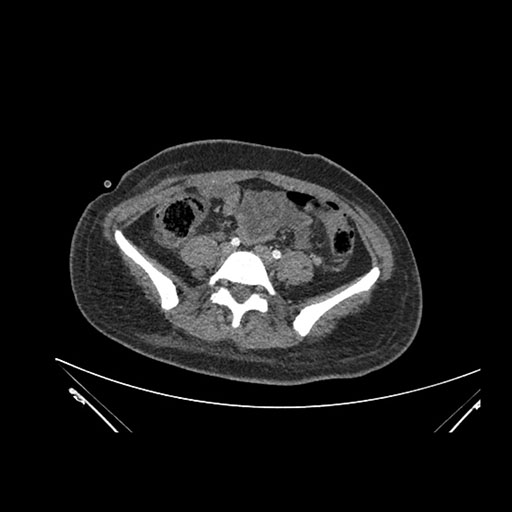

Imaging Analysis

Look through the patient's CT scan to identify any areas of concern for the necessary procedure.

Axial Venous

Based on initial findings, which issue(s) would you be most concerned about?